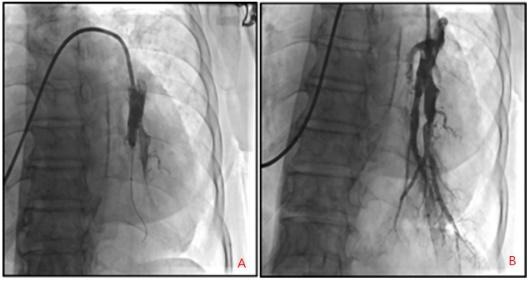

图3:A) BPA前:左肺下叶前、后基底段残根改变;

B) BPA后:血管通畅,远端血管显影